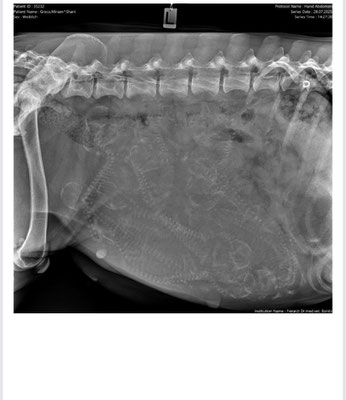

Röntgenbild 1 Woche vor Geburt, na? wieviel Welpen werden wohl erwartet :-)